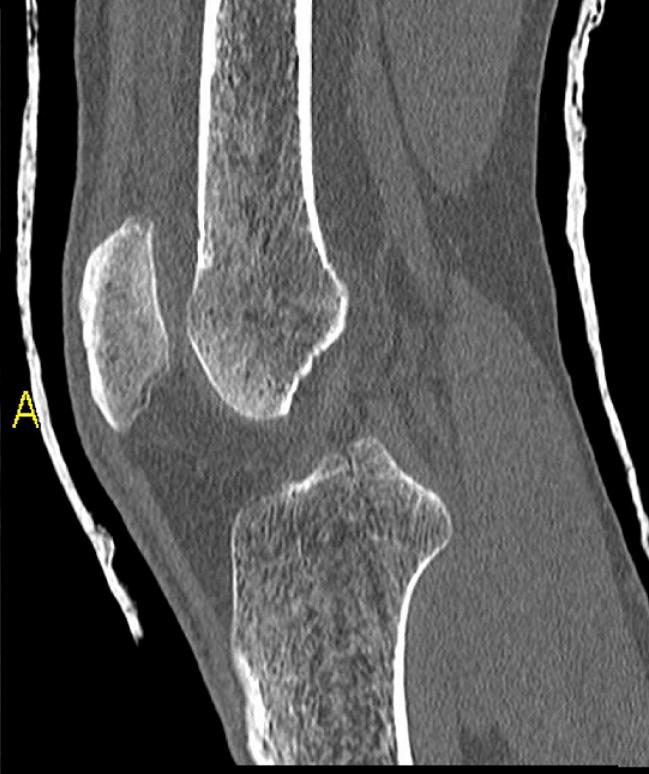

Seltenere Einsatzbereiche der lokalen Ablationsverfahren sind Knochentumoren, Lungentumoren, Nierentumoren und Mammatumoren.

In der Klinik für Diagnostische und Interventionelle Radiologie und Nuklearmedizin wird die lokale perkutane Tumorablation durch Radiofrequenzablation oder Mikrowellenablation durchgeführt. Dabei handelt es sich um Verfahren, bei denen in einem vorher definierten Bereich des Körpers Gewebe durch die Zufuhr von großer Hitze zerstört wird. Klassischstes Beispiel ist die lokale Zerstörung einer bösartigen Raumforderung. In den erwünschten Zielgebieten entstehen sog. Hitzenekrosen oder Koagulationsnekrosen. Antrieb für die starke Hitzeentwicklung ist eine Form von Hochfrequenzstrom bzw. ein Mikrowellengenerator, ähnlich dem Verfahren wie es heute auch beim Veröden von Gefäßen im Rahmen von Operationen genutzt wird. Oberstes Ziel ist es, eine möglichst große Koagulationsnekrose zu erzeugen, ohne dabei dem restlichen Organismus in irgendeiner Weise zu schaden. Wir verwenden für die Radiofrequenzablation bei uns ein System mit sehr dünnen Aufspreizelektroden und einem leistungsstarken 460 Kilohertz-Generator (Video). Bei diesem technischen Verfahren erreicht man Spitzenleistungen von 250 Watt. Der Mikrowellenablator stimuliert Wassermoleküle. Dabei entsteht kinetische Reibung und Hitze, die das Gewebe verkocht. Verschiedene Wellenlängen erzeugen einen unterschiedlichen Wirkungsradius und damit auch einen unterschiedlichen Hitzeradius.

Etwa 2,5 cm bis 3,5 cm große Gewebsbereiche lassen sich pro Elektrodenposition mit beiden Varianten zerstören. Nach etwa einer Viertelstunde ist das Gewebe im Bereich der eingebrachten Ablationssonde vollständig zerstört. Während einer Ablation wird mit Hilfe einer computertomographischen Untersuchung stets die Lage der Sonde kontrolliert, um eine Zerstörung von gesundem Gewebe zu vermeiden.